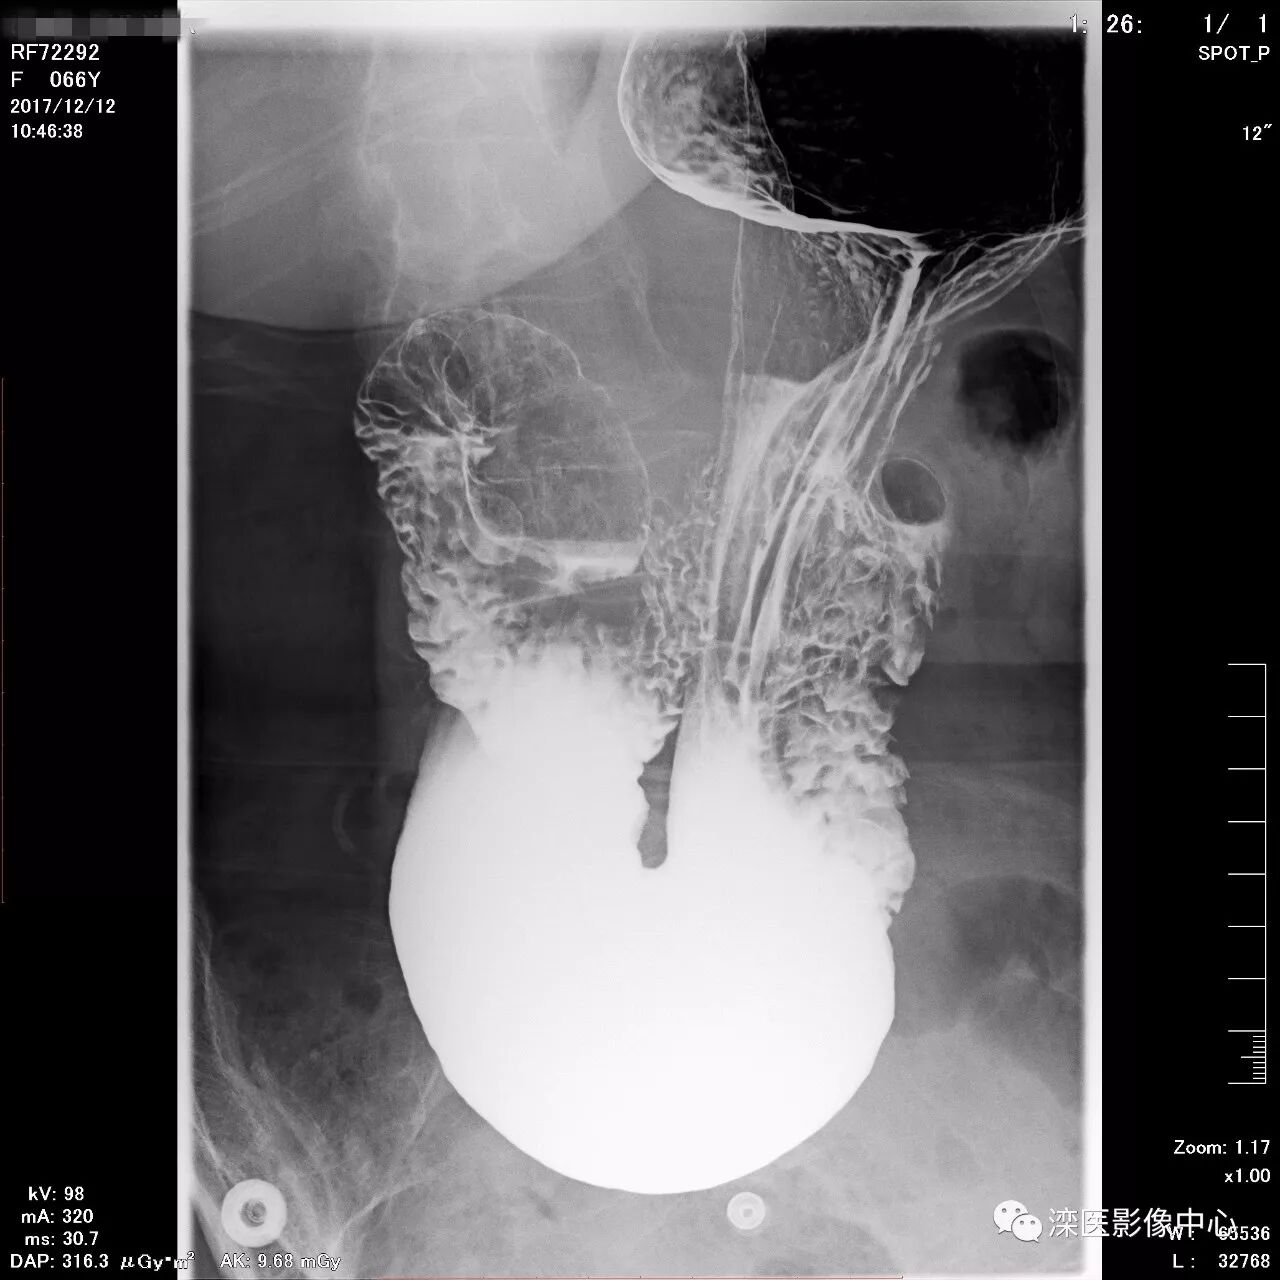

正位,显示食管、贲门及喉咽部的粘膜像)

(左前斜位,显示食管、贲门的粘膜像

(右前斜位,显示食管、贲门的粘膜像)

(以上图像是患者立位+卧位,通过变换体位,多角度显示了贲门胃底、胃体、胃大弯、胃小弯、胃窦、幽门及十二指肠球部、降部、水平部、升部的粘膜像和充盈像。本例患者女性,66岁,此次检查可以清晰显示胃小区结构,检查中发现患有慢性胃炎、胃下垂、十二指肠降部憩室)